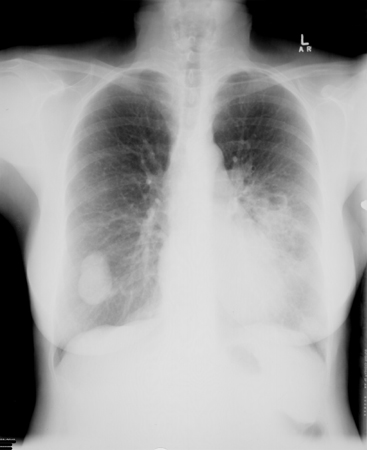

[Figure caption and citation for the preceding image starts]: ფილტვის ბიბაზალური კონსოლიდაცია, გამოწვეული Cryptococcus neoformans-ითრადიოლოგიის დეპარტამენტის კოლექციიდან, The Prince Charles Hospital, Chermside, Brisbane, Australia; გამოიყენება ნებართვით [Citation ends].